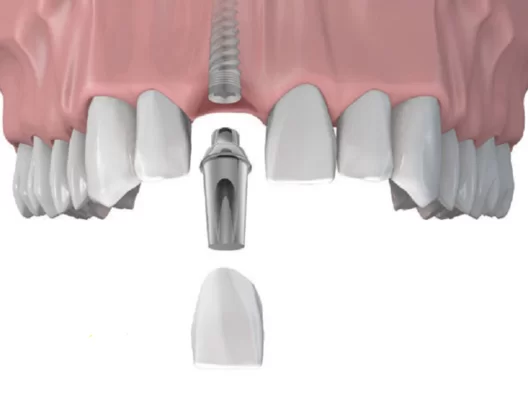

Implant là một vít nhỏ có kích cỡ bằng một chân răng thật được làm bằng Titanium và đặt trong xương hàm thông qua phẫu thuật. Nếu bạn bị mất răng (một hoặc nhiều cái), muốn làm răng giả nhưng vẫn muốn bảo tồn các răng khỏe còn lại, hồi phục khả năng ăn nhai tương đương răng thật nhưng vẫn đảm bảo hoàn toàn tính thẩm mỹ, bác sĩ sẽ tư vấn bạn trồng Implant.

Quy trình trồng Implant gồm có 2 bước. Đầu tiên, các bác sĩ sẽ thăm khám, sau đó cấy ghép 1 trụ Titanium vào xương hàm để thay thế cho chân răng đã mất. Trong khoảng thời gian từ 4 – 6 tháng sau, khi trụ Implant đã được tích hợp vững chắc vào xương hàm, bạn sẽ được gắn phục răng sứ trên trụ đã ghép.

Như vậy Implant được hiểu như “chân răng nhân tạo” nâng đỡ cho răng sứ bên trên. Phục hình trên Implant sẽ được làm đúng theo hình dạng và kích thước của răng thật, đem lại cảm giác dễ chịu và khôi phục được đến 90% khả năng ăn, nhai như răng thật.